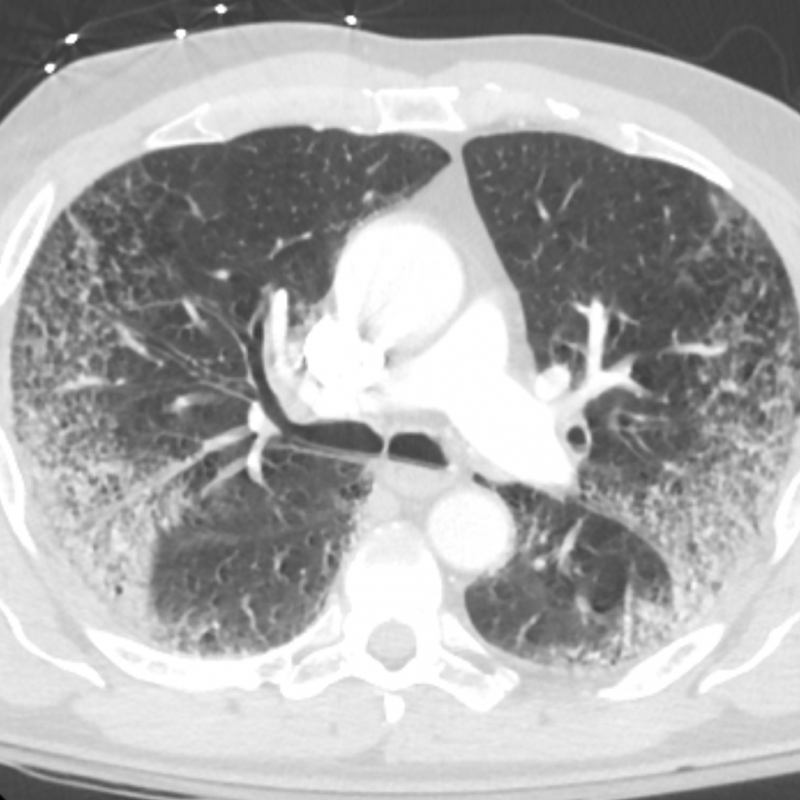

Age: 56

Sex: Male

Indication: Acute respiratory failure

Sample ReportBilateral peripheral airspace disease for which the primary diagnostic considerations include atypical infection, noncardiogenic edema, eosinophilic pneumonia, and chronic interstitial lung disease. Consider chest CT for further evaluation. No pleural effusion.